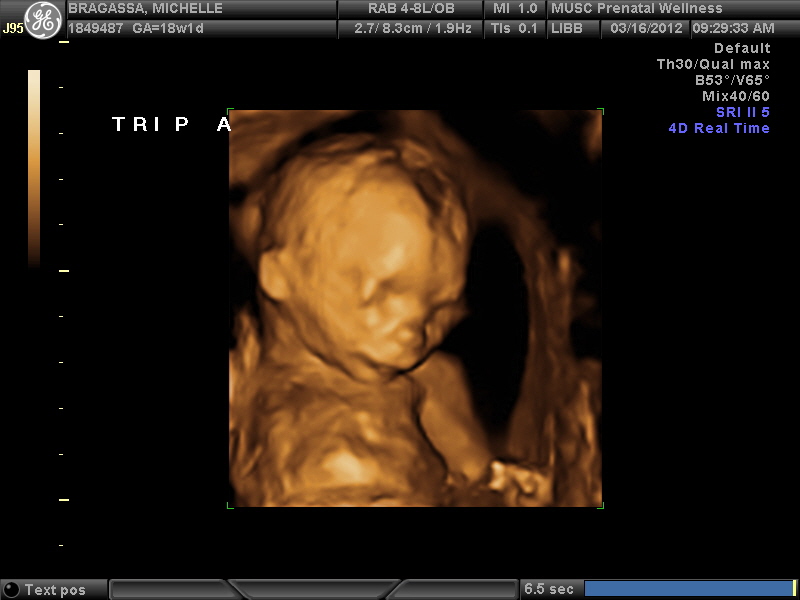

On March 16 (18 weeks, 1 day pregnant), Brian and I went to a 3 hour long ultra sound appointment followed by a doctors visit to check on the status of all the babies.  At this appointment, we were also able to find out the sex of all the babies which like I said above, is 2 girls and a boy.  Obviously, we would have been happy with anything, but I'm not gonna lie, I think we were both excited to see that there is a mix in there.  The funny thing was that when the ultra sound tech started the ultra sound, she tried to look at Baby A first to determine the sex, but he/she didn't want to cooperate so she moved on to Baby B.  Baby B cooperated and is a GIRL!!  Then she moved on to Baby C and after a few minutes, we were able to get a good view and see that Baby C is a GIRL too!!  This is the point where Brian started to sweat I think...I also think he said something along the lines of, "Well, that's two weddings!".  Haha!  Since there's so many babies in there, I sometimes get confused at which one I'm looking at on the screen...it really is like a cluster of babies in there and it's super easy to get lost and not know which one is which!  Anyway, like I said, I get kind of confused about what baby is where, so when the ultra sound tech went back to Baby B, when I thought she was looking at Baby A, I looked at the screen, noticed it was a girl, then looked at Brian and said, "It's 3 girls!".  I seriously think he almost passed out...he was convinced that there had to be at least one boy in there!  Fortunately, the ultra sound girl heard me and interrupted saying "No, no, no!  This is Baby B...there's still hope for a boy!".  Luckily, this time Baby A decided to cooperate and wiggled around so we could get a good look and what do ya know...it is a BOY!  Here's some pictures from the ultra sound!

Hand in front of his face!

That's better!  It looks like his head has a whole in it which is kinda true...that's partly where the soft spot is and partly because he was pushed up against the uterine wall.